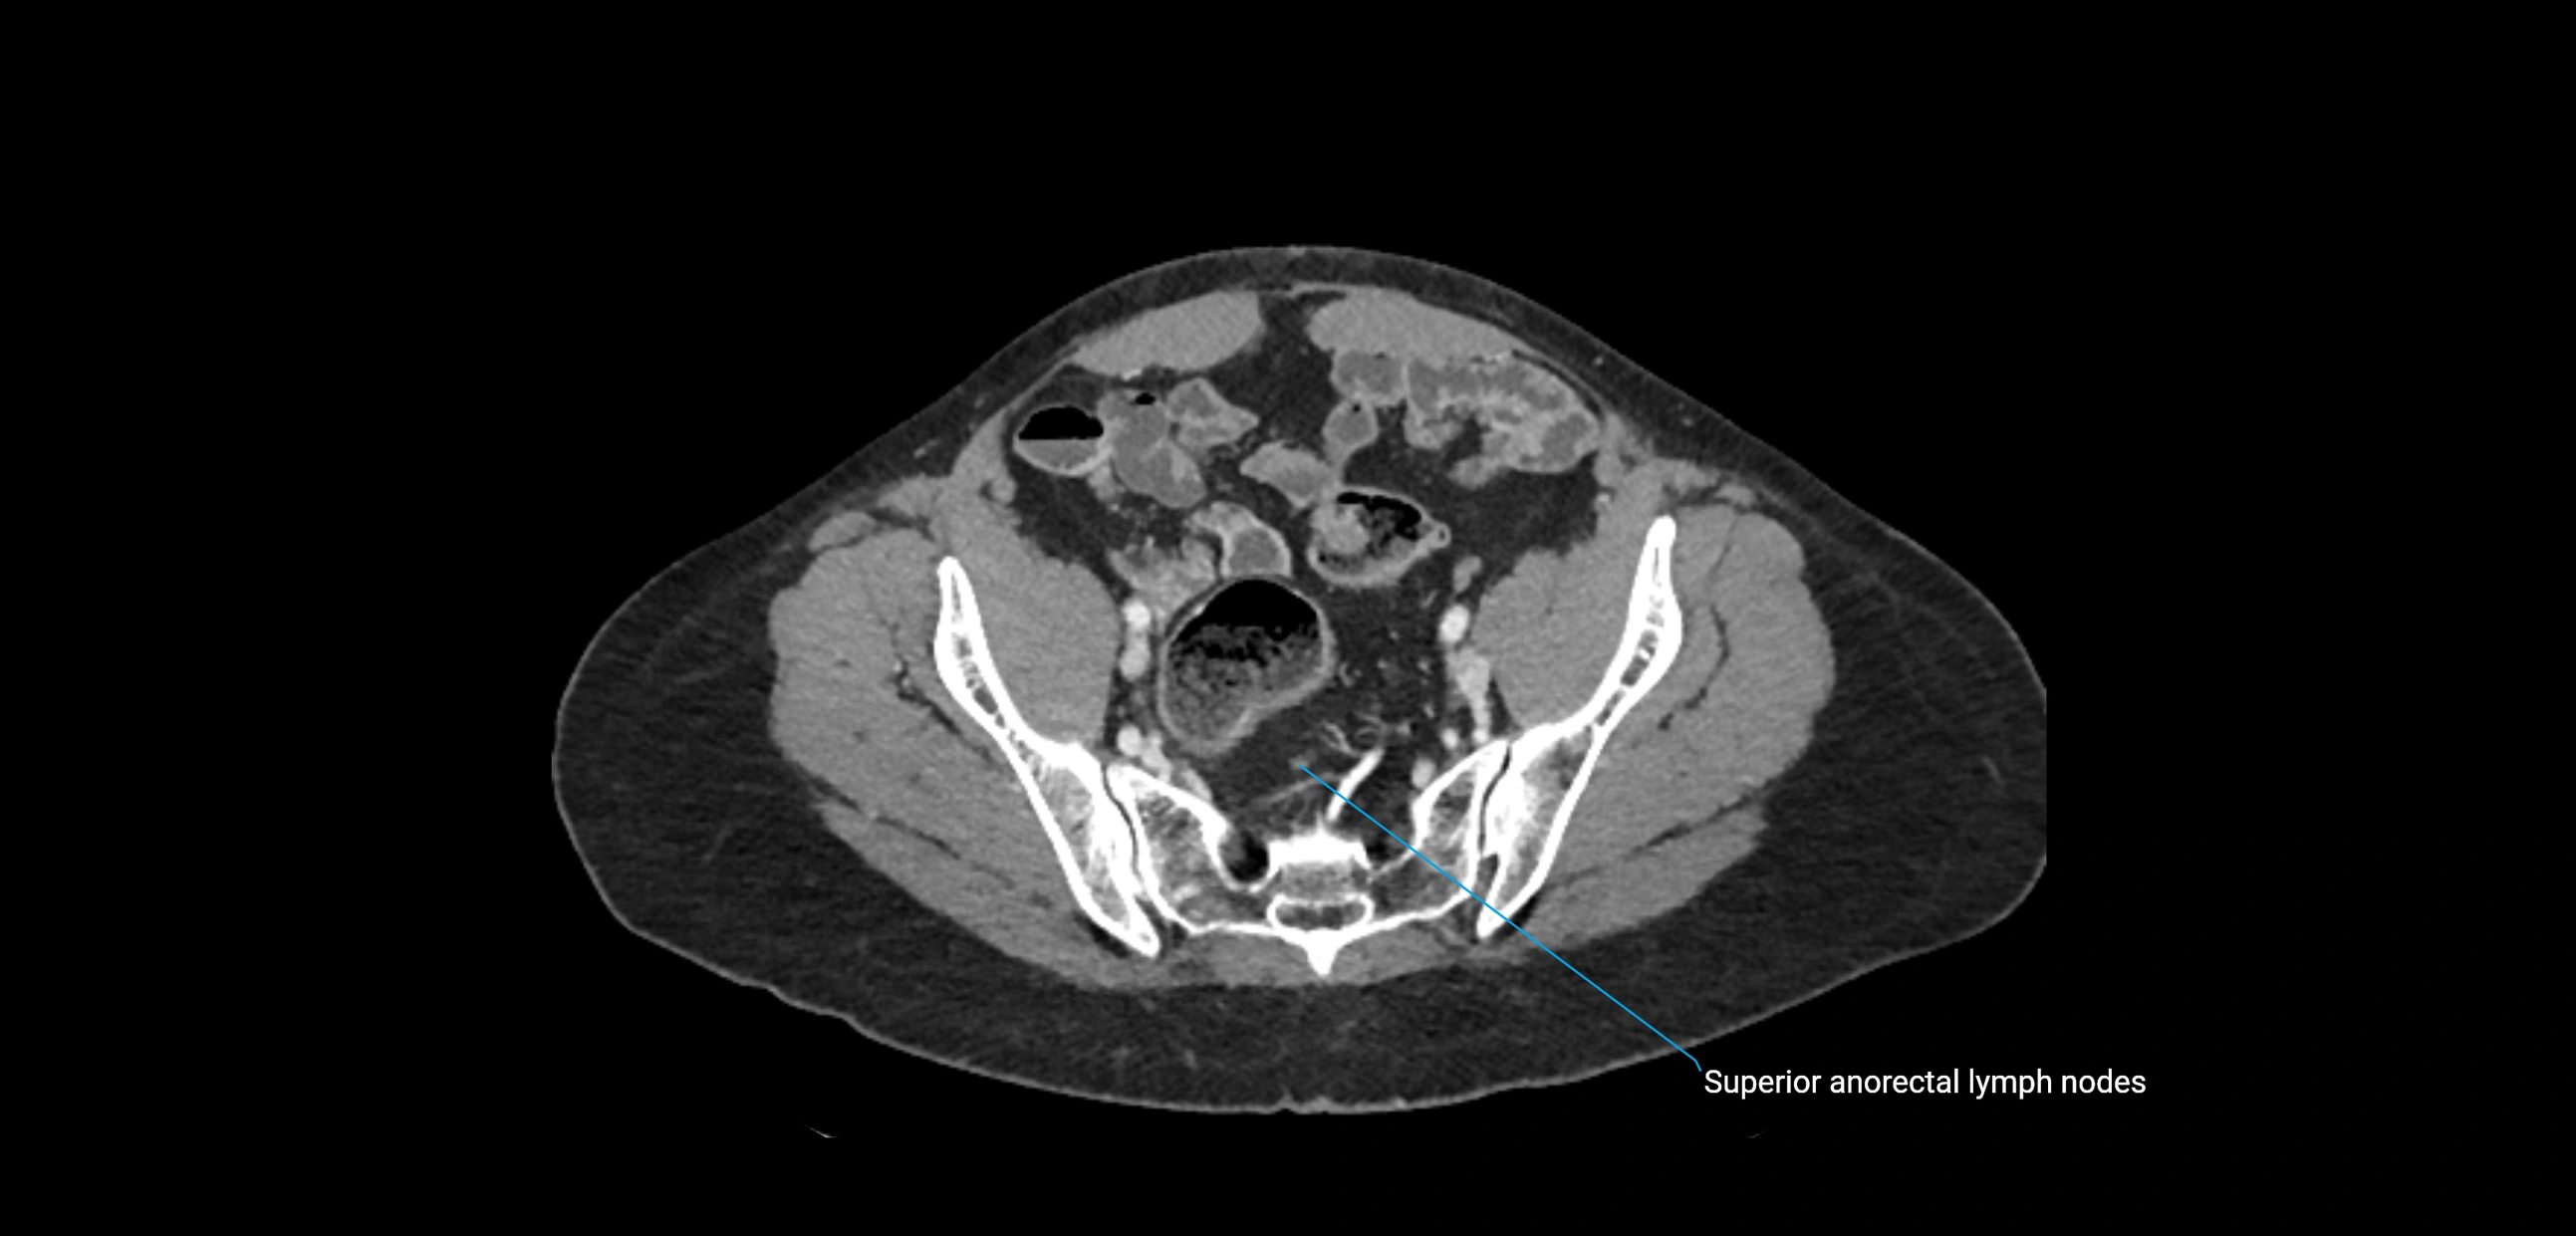

CT image

image